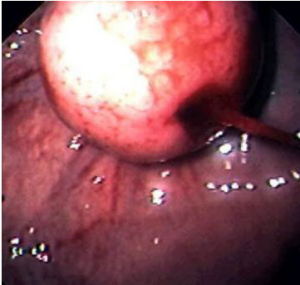

對於胃平滑肌瘤的診斷除臨床上出現上消化道出血、腹痛腹部包塊者應疑及該病外,主要依靠X線及胃鏡檢查。X線檢查可見孤立的圓形或橢圓形的充盈缺損腫瘤周圍黏膜正常。充盈缺損區有龕影提示平滑肌瘤有潰瘍腫瘤向胃外突出時可見胃壁畸形,或呈外在壓跡樣缺損胃鏡檢查可見半球形或球形隆起黏膜緊張光滑色澤正常頂部可有缺血壞死性潰瘍術前確診較困難常需要才能證實。

5.胃鏡檢查 普通內鏡可以直觀腔內型腫瘤的形態大小及生長特點,亦可直接行組織活檢以取得病理學證據,甚至可經胃鏡行胃平滑肌瘤摘除術但對於沒有侵犯黏膜的腫瘤及腔外型腫瘤則意義不大可見半球形或球形隆起,表面黏膜 緊張光滑,色澤與周圍黏膜相同,頂部有時可出現缺血壞死性潰瘍術前確診較困難,常需要組織學檢查才能證實。